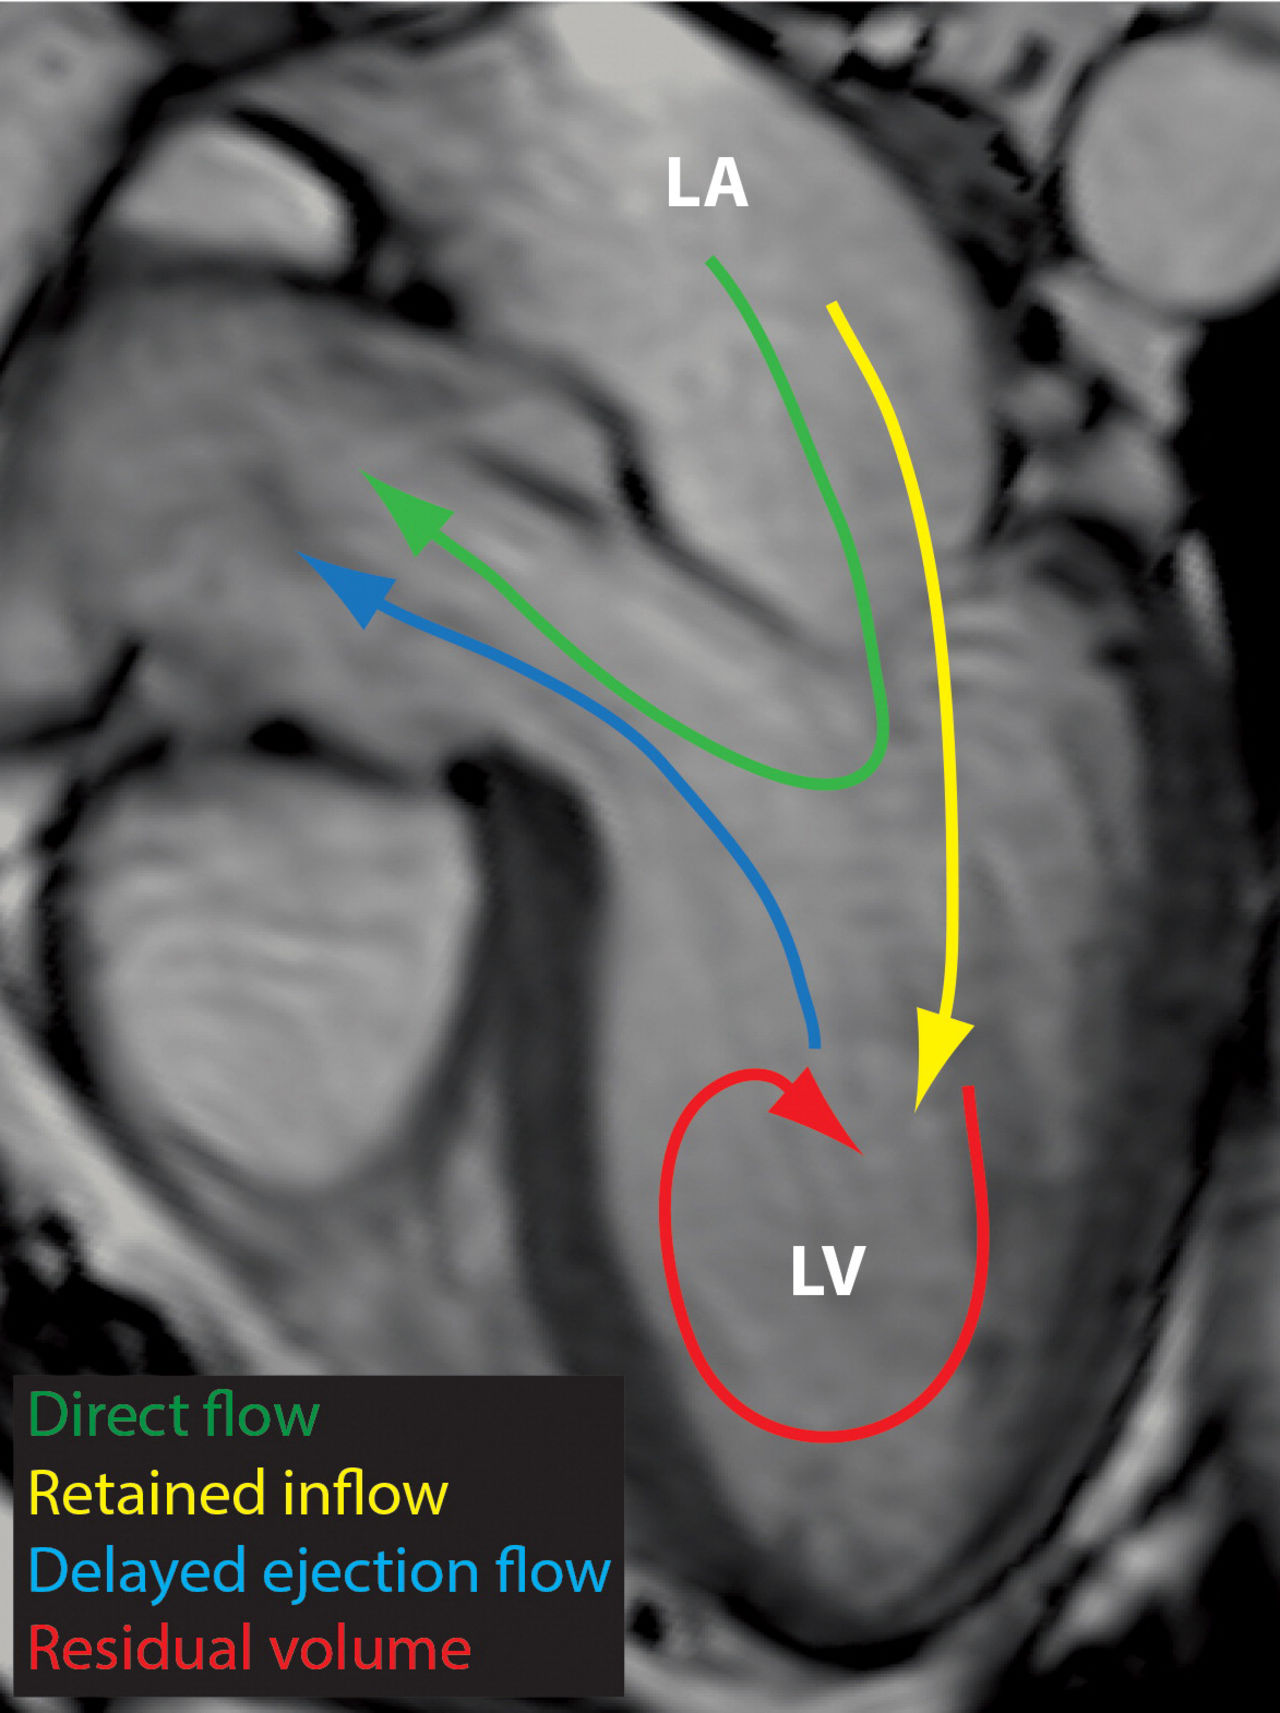

Advanced computed tomography (CT) creates amazing visualization of the beating heart. However, the complex interactions of blood flow are not fully reflected by these images. This project aims to extract blood flow data from CT images of the heart using image-based simulations. The goal is earlier and more accurate detection and improved management of cardiac diseases.

Advanced computed tomography (CT) allows for amazing visualization of the human body including the beating heart. However, the complex interactions of blood flow, which is crucial in the diagnosis and treatment planning of many diseases, are not fully reflected by these images. Magnetic resonance imaging (MRI) and ultrasound are able to measure functional data like blood flow, but at a low resolution. Furthermore, these techniques are not able to predict the changes in blood flow after surgical treatment.

This project aims to extract blood flow data from CT images of the heart using image-based simulations. The goal is earlier and more accurate detection as well as improved management of cardiac diseases.